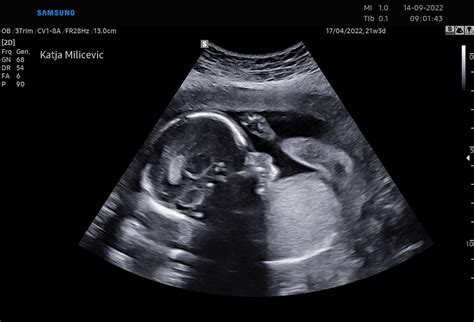

Nadaljnji razvoj poteka z neverjetno hitrostjo. V 32. tednu plod doseže težo med 1600 in 1800 grami ter dolžino 42 cm. V tem tednu se priporoča kontrola rasti in kondicije ploda, ki s pomočjo ultrazvoka oceni telesno težo, količino plodovnice, zrelost posteljice ter pretok krvi skozi popkovnične žile. Koža postaja rožnata in gladka, na rokah in nogah pa so prisotni nohti. Če bi se plod rodil v tem tednu, bi njegova možnost preživetja znašala že 95 %.

Velikost trebuha je posredno pokazatelj rasti ploda, vendar za objektivno oceno potrebujemo meritve. Pri 34 tednih bi morala biti razdalja od zgornjega roba sramne kosti do vrha maternice vsaj 32 cm. Če je ta meritev manjša od 30 cm, se priporoča kontrolni ultrazvok za merjenje ploda. Med 18. in 36. tednom nosečnosti je razdalja med simfizo in fundusom relativno linearna in se lahko izračuna kot število tednov nosečnosti minus 2 cm, z odstopanjem +/- 2 cm.